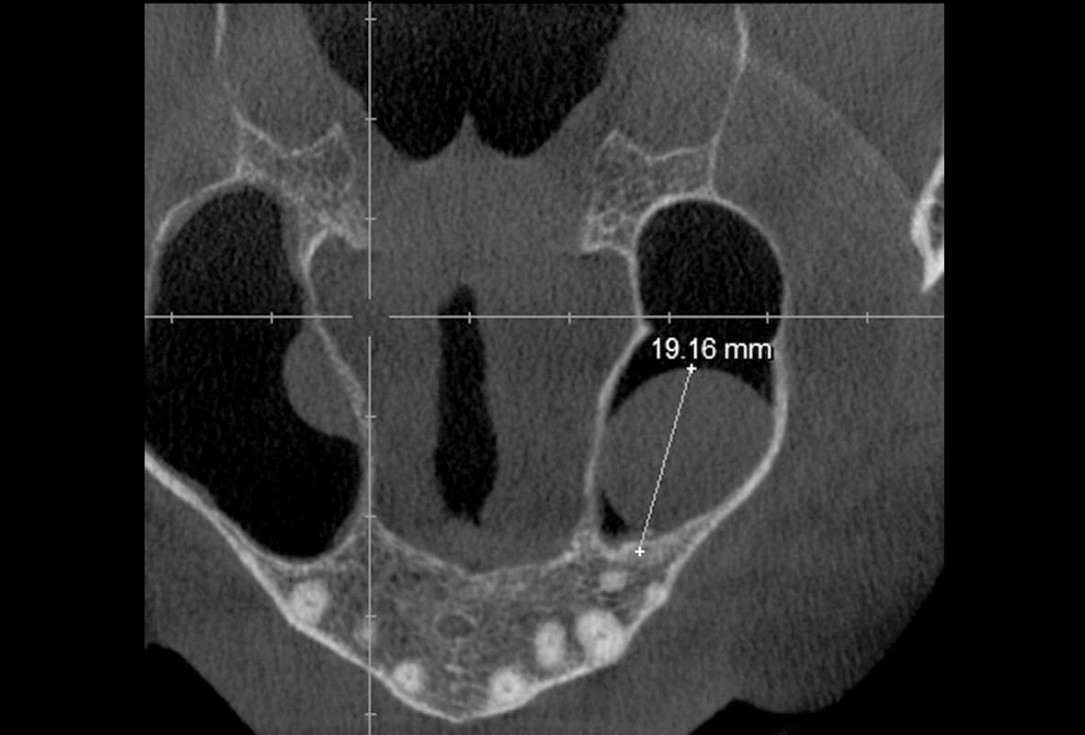

02/35 - CBCT shows maxillary sinus cystMaxillary sinus cyst removal using the Crocodile Technique and subsequent lateral sinus lift - Dres. C. Scognamiglio and A. Perucchi

03/35 - CBCT shows maxillary sinus cystMaxillary sinus cyst removal using the Crocodile Technique and subsequent lateral sinus lift - Dres. C. Scognamiglio and A. Perucchi